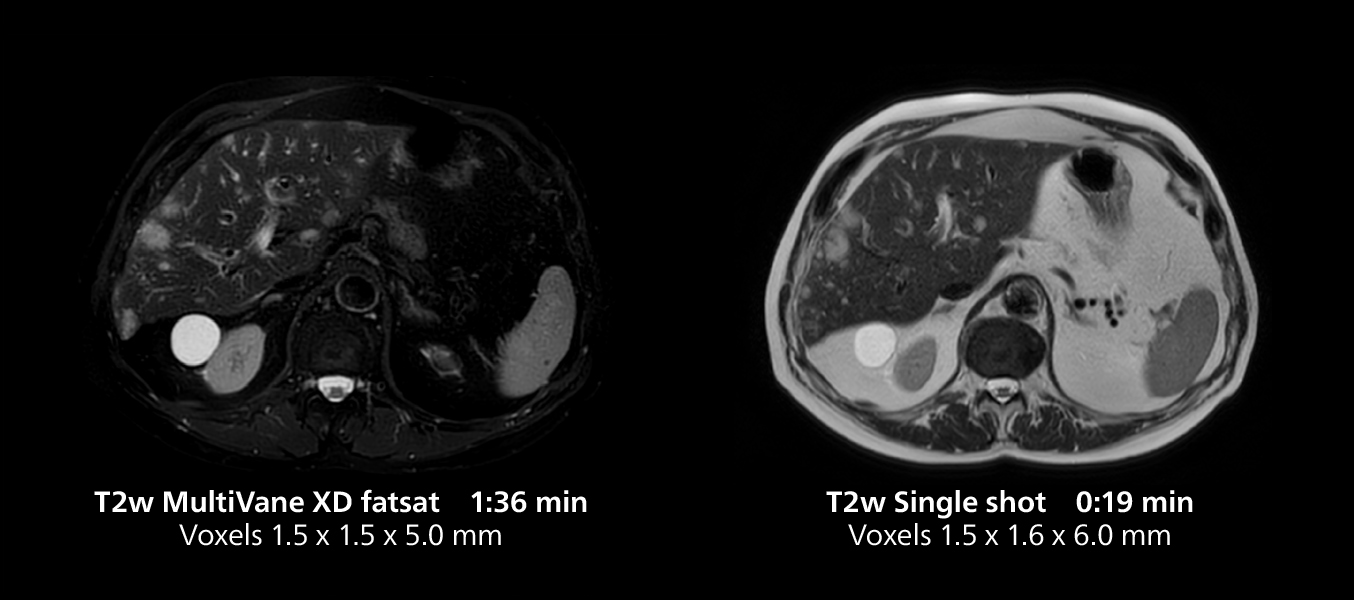

This case includes 3D free breathing and 4D dynamic free breathing MRI of a metastasized liver. A high quality fatsat sequence with good resolution is obtained in 1:36 minutes with T2-weighted MultiVane XD.